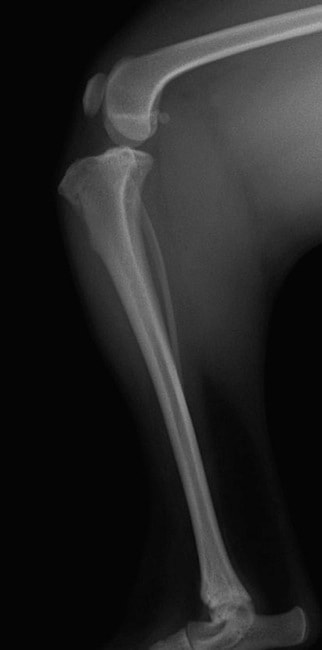

■ 症例22 ポメラニアン 1歳5か月 去勢雄

左後肢の挙上を主訴に来院した。整形学的検査、レントゲン検査より左右の膝蓋骨脱臼(左GradeⅡ〜Ⅲ、右Grade Ⅱ)を認めた。また、脛骨の前方引き出し試験の際に、引き出し兆候は認められないものの、疼痛が認められたため、前十字靭帯の損傷が疑われた。術中における、目視および関節内の操作によって、前十字靭帯の損傷や過伸展といった異常が認められなかったため、膝蓋骨脱臼の整復のみ実施した。手術手技は縫工筋及び内側広筋の解放、脛骨粗面の外側転位、滑車ブロック形造溝術、内外側関節包の縫縮を実施した。本症例は跛行もなく経過良好である。しかし、頸骨高平部の角度(TPA)が 右26.2°、左24.9°であり、解剖学的に前十字靭帯損傷のリスクが高いことから今後の経過に注意が必要である。